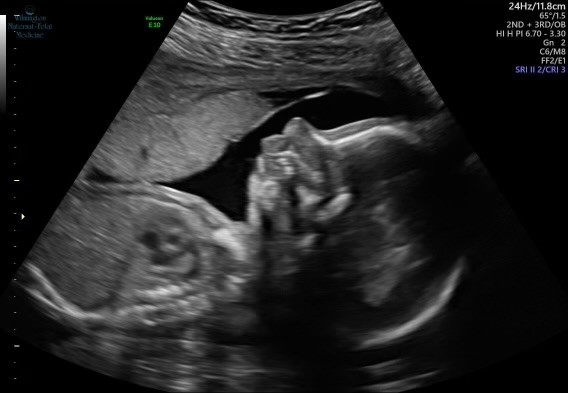

Soon it was time for the 20-week anatomy scan – an ultrasound that checks for birth defects to ensure the baby is developing well. With COVID-19 restrictions, only Heather was allowed to attend the appointment in person.

Over FaceTime, Phil watched as the ultrasound technician looked at their baby, then “got kind of quiet.”

Soon, the technician left and returned with a genetics counselor who explained that the baby’s chin appeared underdeveloped – sloping back toward the neck, instead of jutting out. (A condition called micrognathia.)

Phil, who works for a medical device company, was aware of the term – and its risks. “They said it was like 10% of a normal chin,” Phil said. “And sometimes that can be a precursor to a lot of different issues.” Many of them serious.